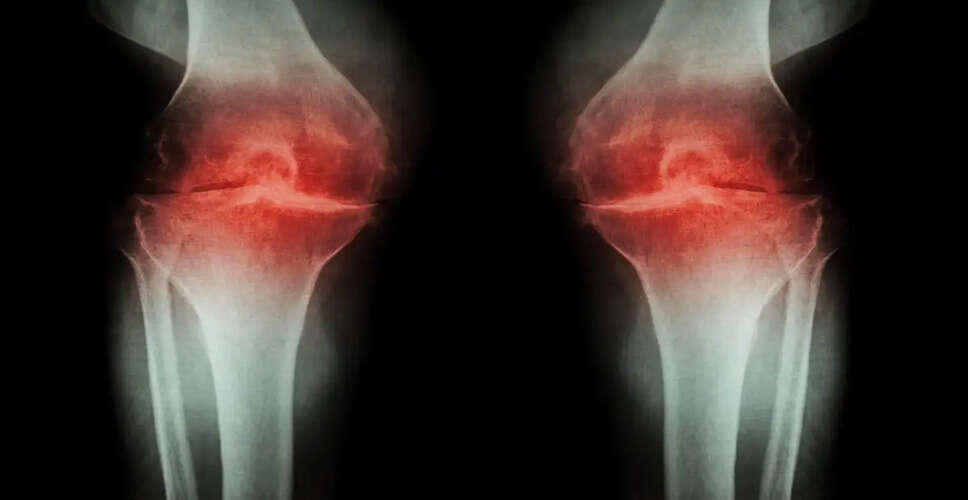

Stress is detrimental to bones. Elevated cortisol levels hinder calcium absorption and bone repair. Prolonged stress can weaken bones, increasing the risk of osteoporosis and fractures, particularly in women due to hormonal imbalances.

Stress and anxiety also compromise joint health. Excessive stress can heighten inflammation in the body, posing additional challenges for arthritis patients. Physical activity may decrease due to stress, leading to increased discomfort.